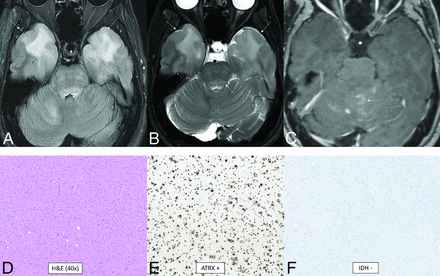

Diffuse pediatric-type high-grade glioma, H3 wild-type and IDH wild-type. MR images demonstrate diffusely infiltrating masses in the bilateral temporal lobes with mild mass effect, T2-FLAIR (A) and T2-hyperintensity (B, anterior arrows), and no enhancement (C). There is additional T2-FLAIR and T2-hyperintensity in the dorsal pons and posterior fossa leptomeningeal enhancement (posterior arrows). Histology reveals a high-grade diffusely infiltrating astrocytoma with high mitotic activity (D). The tumor shows ATRX retention (E) and wild-type IDH status (F) on immunohistochemical stains. Whole-genome methylation analysis showed a match to diffuse pediatric-type high-grade glioma. The tumor was H3 wild-type and IDH wild-type and had a TERT promoter mutation, which was identified on the neuro-oncology targeted next-generation sequencing panel.

Diffuse pediatric-type high-grade glioma is another of the 4 pediatric high-grade glioma types. It does not have an assigned WHO grade or a single defining molecular or genetic feature.1 About half of tumors previously classified as “pediatric glioblastoma” demonstrate mutations of histone 3 or uncommonly IDH1/2. The remaining heterogeneous tumors now fall under this new classification. The 3 recognized subtypes are characterized by MYCN, PDGFRA, and EGFR amplifications with numerous coexisting genetic abnormalities described.24 The MYCN subtype has high cellularity and mitosis, spindle, and epithelioid cell components; necrosis; and microvascular proliferation.25,26 The median age at diagnosis is 8–11 years (range, 2–18 years).24 There is no sex predilection overall, but there is a slight male predominance for the EGFR subtype (male/female ratio, 1.6:1).24 The location is usually supratentorial, with the posterior fossa approaching 20% of cases, depending on subtype.24 The MYCN subtype classically shows a solid, enhancing, diffusion-restricting, well-marginated temporal lobe mass abutting the meninges with tumoral necrosis, rare hemorrhage, and no calcifications.25,26 A tumor in the pons has greater enhancement and diffusion restriction compared with a diffuse midline glioma, H3 K27-altered.25 Figure 5 demonstrates a less-typical case without enhancement of the primary tumors.